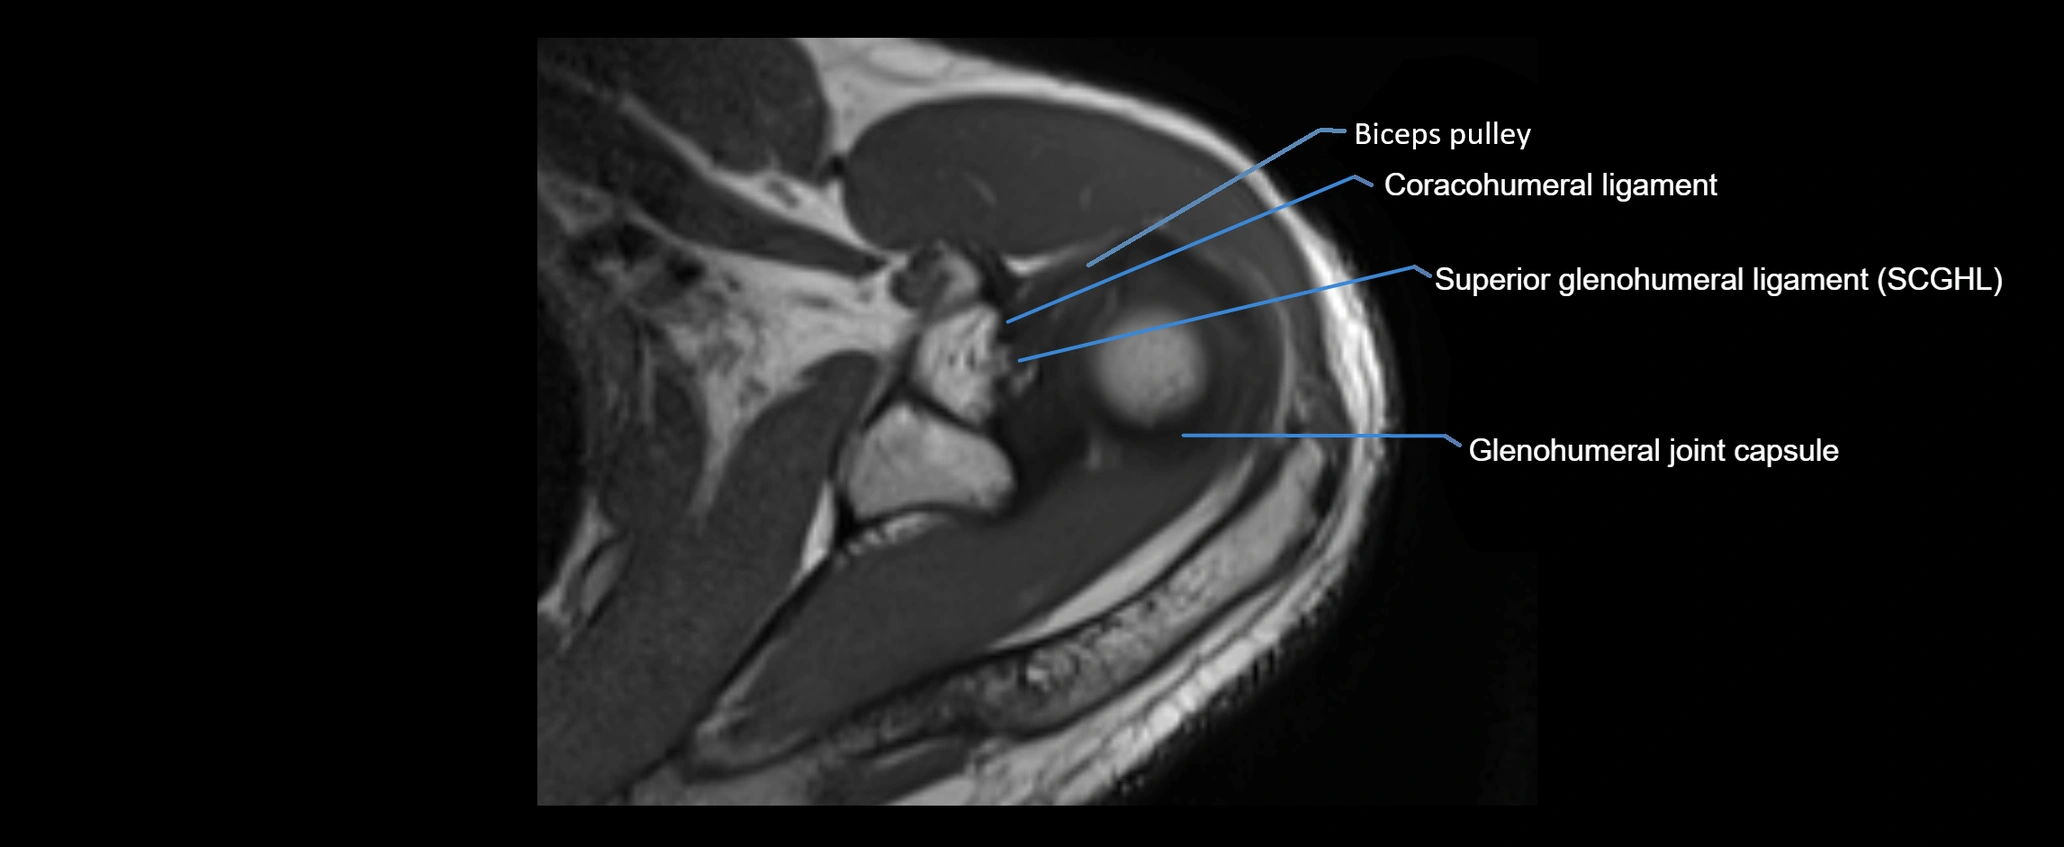

MRI images

image